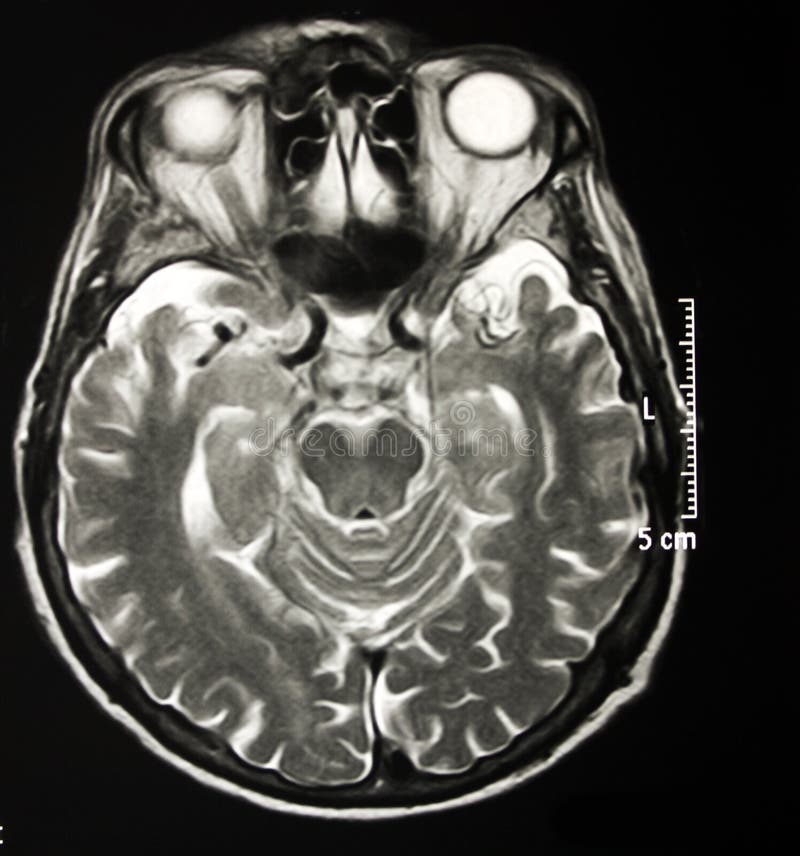

Lista muestra hermosas imágenes de resonancia magnética cerebral normal y anormal dinosenglish.edu.vn para que puedas explorar más en detalle.

resonancia magnética cerebral normal y anormal Pin en NEUROCIENCIAS resonancia magnética de cerebro Resonancia magnética (RM) de cerebro, corte axial ponderado en T2: la … VIDEO Nueva mancha en la Resonancia

Engineer Team : RESONANCIA MAGNETICA Magnetic Resonance Imaging – Clinical Images Hallazgos por resonancia magnética cerebral de nuestro paciente. M, 21 … Imágenes por resonancia magnética anormales como predictoras de mal … Imágenes por resonancia magnética anormales como predictoras de mal … Lesiones en resonancia magnética (RM) del encéfalo y la médula espinal … Pin en Resonancia Magnética del Encéfalo A) Resonancia magnética cerebral (RMC) mostrando infartos en … Caso 1: Edema cerebral visualizado mediante RM. (A) Secuencia T1 plano … Rascacielos dormir pasta tac y resonancia diferencias retrasar … Pin on Apuntes de Enfermería y T.C.A.E Resonancia magnética cerebral secuencia T2, que muestra lesión … Meningitis aguda en la enfermedad de Behçet | Reumatología Clínica Resonancia magnética coronal normal del cerebro Fotografía de stock – Alamy Imágenes de resonancia magnética, la imagen de la cabeza en diferentes … Resonancia magnética cerebral A) protocolo T1 sagital (Caso 1). Se … Resonancia magnética cerebral. Secuencia T1 corte sagital. Atrofia … Resonancia magnética de cerebro, cortes axiales, secuencias T2. Señal … Resonancia magnética de cráneo. A y B) Cortes axiales FLAIR … Resonancia magnética (RM) de cerebro, corte axial ponderado en T2: la … RM cerebral: Interpretación paso a paso | Kenhub Resonancia magnética de cerebro, cortes axiales, secuencias T2. Señal … De Resonancia Magnética De Cerebro Foto de archivo – Imagen de arteria … Top 107+ Imagenes de resonancia cerebral normal – Destinomexico.mx -Imagen por resonancia magnética del cerebro. a) Cortes sagital y axial … resonanCia magnétiCa Cerebral donde se observa hiperintensidad a nivel … MRI (Imagen de resonancia magnética) – Tomografía computarizada de la … Meningioma – NCI Imágenes por resonancia magnética coloreadas del cerebro sano del … Resonancia magnética cerebral en secuencia FLAIR, que muestra lesiones … Contraste resonancia magnetica cerebral – senturinthegreen Relación de los espacios de Virchow-Robin con la enfermedad de … Gliomatosis cerebral – Instituto Nacional del Cáncer Pin en Neurology. Recomendaciones para la utilización e interpretación de los estudios de … Fotografía De La Proyección De Imagen De Resonancia Magnética Del … atmósfera Dirigir Cumplir anatomia resonancia magnetica Desarrollar … Pin en #MEDICINA,#SALUD Resonancia magnética de la nasofaringe De Resonancia Magnética De Cerebro Foto de archivo – Imagen de polilla … Atrofia cortical global de predominio parietal en la Resonancia … Resonancia magnética cerebral | Download Scientific Diagram Neuroblog: Resonancia magnética cerebral en la trombosis crónica de … De Resonancia Magnética De Cerebro Imagen de archivo – Imagen de … ¿Cuáles son los riesgos de la resonancia magnética? – Integra Salud … Resonancia magnética cerebral al decimocuarto día de ingreso: área … Resonancia magnética. Corte axial mostrando área infartada en el … Resonancia magnética cerebral del paciente AV evidenciando lesiones en … -Ressonância magnética de encéfalo mostrando múltiplas imagens … Resonancia magnética cerebral secuencia FLAIR (Fluid Attenuated … Resonancia magnética cerebral con protocolo de epilepsia, en sección … Resonancia magnética cerebral en corte sagital. Se observa una evidente … Resonancia magnética craneal en la que se evidencian lesiones … Logran visualizar el cerebro a detalle más completo tras una resonancia … Así decide el cerebro la severidad de un castigo De Resonancia Magnética De Cerebro, Imagen de archivo – Imagen de … A) Resonancia magnética cerebral; Secuencia Tof: oclusión de arteria … Un estudio asocia la ansiedad con la aparición rápida del Alzheimer IMÁGENES DE 18 F-PR04.MZ PET FUSIONADA CON RESONANCIA MAGNÉTICA … Imágenes por resonancia magnética anormales como predictoras de mal … Tumores de la región pineal – Instituto Nacional del Cáncer Epilepsia: una historia de voces y fantasmas | Neurología Contribución de las imágenes de resonancia magnética por tensor de … Resonancia magnética secuencia T2 plano coronal de quiste epidermoide … Resonancia Magnética Cerebral del paciente: a. Aumento de… | Download … Resonancia magnética cerebral 2022 Síndrome de hemiconvulsión-hemiplejía-epilepsia. Seguimiento de un caso … Enfoque Radiologico: La resonancia magnética permite detectar lesiones … Resonancia magnética craneal T1 con contraste que muestra angiomatosis … guidewiz – Blog Resonancia magnética cerebral, secuencia SWI. Ribete hipointenso en la … resonAnCiA mAgnétiCA de ColumnA Con gAdolinio. Corte sAgitAl en t1 de … SEMANA 12: FUNDAMENTOS DE RESONANCIA MAGNÉTICA NUCLEAR. INDICACIONES Y … DIAGNÓSTICO DE ESCLEROSIS MÚLTIP Magnetic resonance imaging of the brain – Alchetron, the free social … Resonancia magnética de órbitas | Instituto Radiológico Dr. E Castillo Alteración de la marcha en un paciente post-trasplante hepático Resonancia magnética cerebral de un paciente sano (Ay B) y paciente que … Utilidad de la resonancia magnética craneal para el diagnóstico de la … Resonancia Magnética Del Cerebro El Tumor Cerebral Foto de stock y más … De Resonancia Magnética De Cerebro Imagen de archivo – Imagen de … ABDALLA RADIOLOGIA: NEURINOMA ACUSTICO Atrofia cortical global de predominio parietal en la Resonancia … Resonancia Magnética : Producción de la imagen MRI Brain Scan — Stock Photo © Bunyos30 #18724051 Mri (imagen de resonancia magnética) Monitor con imagen de captura de … Tomografía computarizada vs resonancia magnética: diferencia y … Tumores Cerebrales – Unidad de Neurocirugía RGS Resonancia magnética de la columna, sección sagital. Observe los discos … La resonancia magnética, una técnica imprescindible en el diagnóstico … Perfusión Cerebral por Resonancia Magnética | ¿Qué es? ¿Necesita Contraste? Resonancia Magnética Cerebro A: resonancia magnética, T2 coronal preoperatoria; se observa lesión en … Resonancia magnética cerebral — Foto de stock © Bunyos30 #27340623 La resonancia magnética se perfila como detector de mentiras | Futuro … Resonancia magnética cerebral en T1 con gadolinio, cortes axial (a … MRI brain : show brain tumor at right parietal lobe of cerebrum — Stock … NEUROIMÁGENES EN ENFERMEDAD DE PARKINSON: ROL DE LA RESONANCIA …